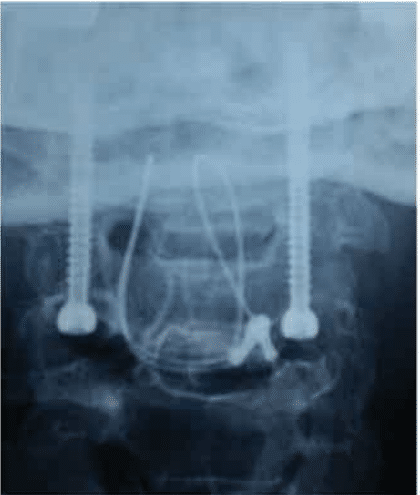

C1-C2 was maintained in extension with C1-C2 trans articular screw fixation with additional wiring of the posterior arch of C1 to C2 and bone grafting was done.